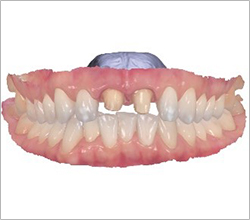

Full-mouth implants are highly advanced treatment

that require precise upper and lower occlusal harmony.

Patients themselves have proven us to be

a clinic specialized in full-mouth implant surgery.

Full-mouth implants are among the more complex dental procedures. They require careful decision-making, precise diagnosis based on each individual condition, and ongoing postoperative care after placement. With extensive experience in full-mouth implant treatment, Seoul The Nature Dental Clinic can provide systematic planning, placement, and follow-up care. Many patients continue to visit us through recommendations as a trusted clinic for full-mouth implants.